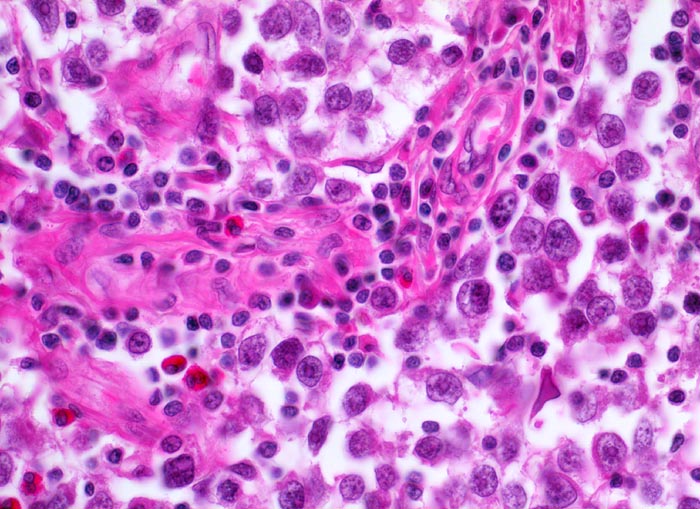

Makroskopisch imponieren Seminome als gut begrenzte weiche crèmefarbene Knoten oder diffuses Intiltrat. Mikroskopisch findet sich eine uniforme Population grosser Zellen mit prominentem zentralem Nukleolus, welche durch schmale Bindegewebssepten voneinander getrennte Nester bilden. Ein leukozytäres Entzündungsinfiltrat, synzytiotrophoblastäre Riesenzellen und Mikroverkalkungen können zusätzlich vorhanden sein. Gelegentlich induziert der Tumor eine ausgeprägte granulomatöse Entzündung. Dies kann zur Fehldiganose einer granulomatösen Orchitis führen.

• Unterschiedlich breite solide Tumorzellstränge aus monomorphen Zellen mit grossen hyperchromatischen Kernen und einem solitären zentralen prominenten Nukleolus. Reichlich helles Zytoplasma mit scharfen Zellgrenzen.

• Schmale bindegewebige Septen mit Kapillaren und lymphoplasmazellulärem Entzündungsinfiltrat.